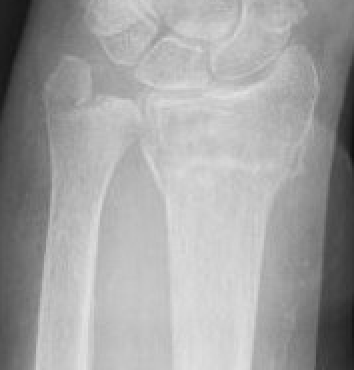

Classification ulna styloid fractures

| Type 1: Tip | Type 2: Base | Type 3: Proximal to styloid |